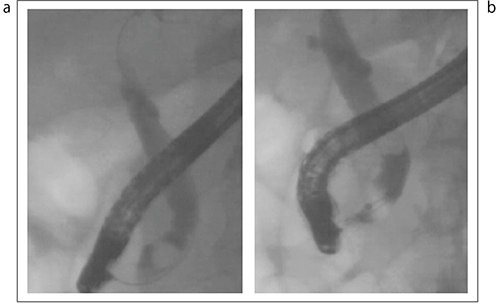

図16の症例は、別のルートからガイドワイヤを進入させ、バスケット操作により結石除去に成功した症例である。

図16 下部胆管ポケットの結石に対するガイドワイヤルート変更例

a:ガイドワイヤを挿入するが、バスケットが開かない

b:ガイドワイヤを外した後、再度対側に挿入した